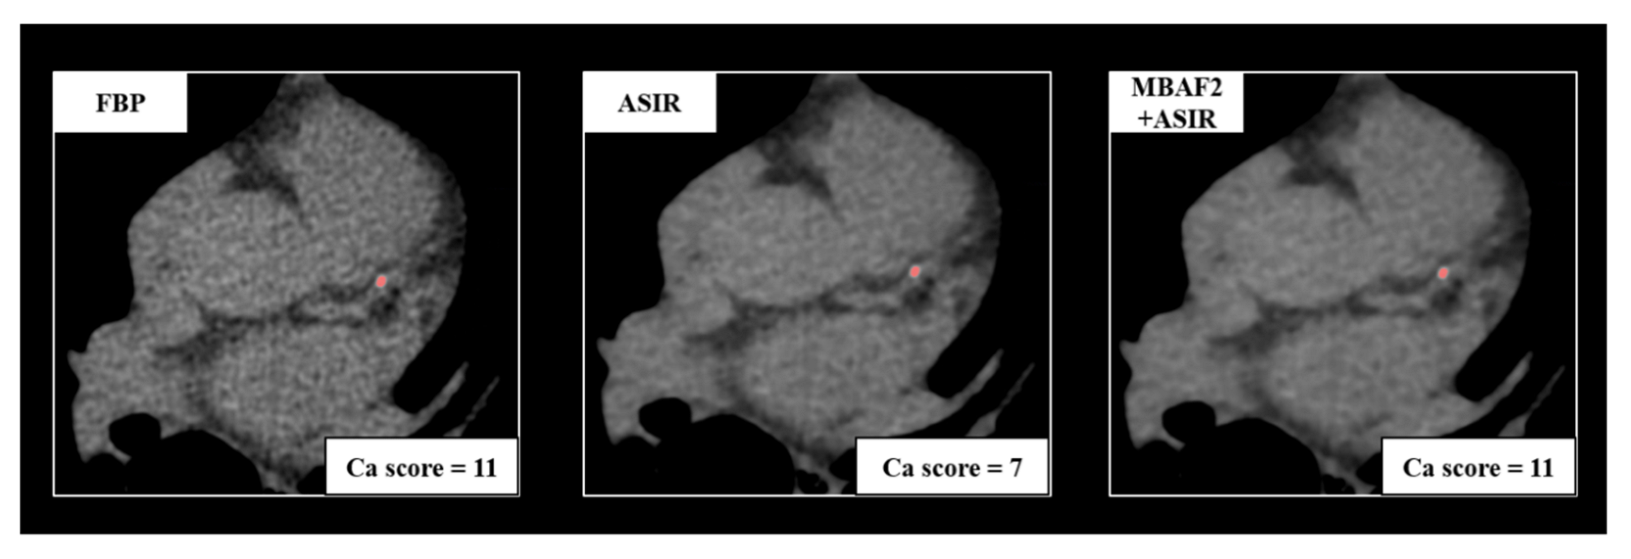

| FBP | ASIR-CV | MBAF2+ASIR-CV | p | |

| Calcium volume (mm3) | 7.0 (0.0–133.25) | 4.0 (0.0–103.5) | 5.0 (0.0–118.5) | <0.001 |

| Agatston score | 17.0 (0.0–324.8) | 9.5 (0.0–286.5) | 11.0 (0.0–288.0) | <0.001 |